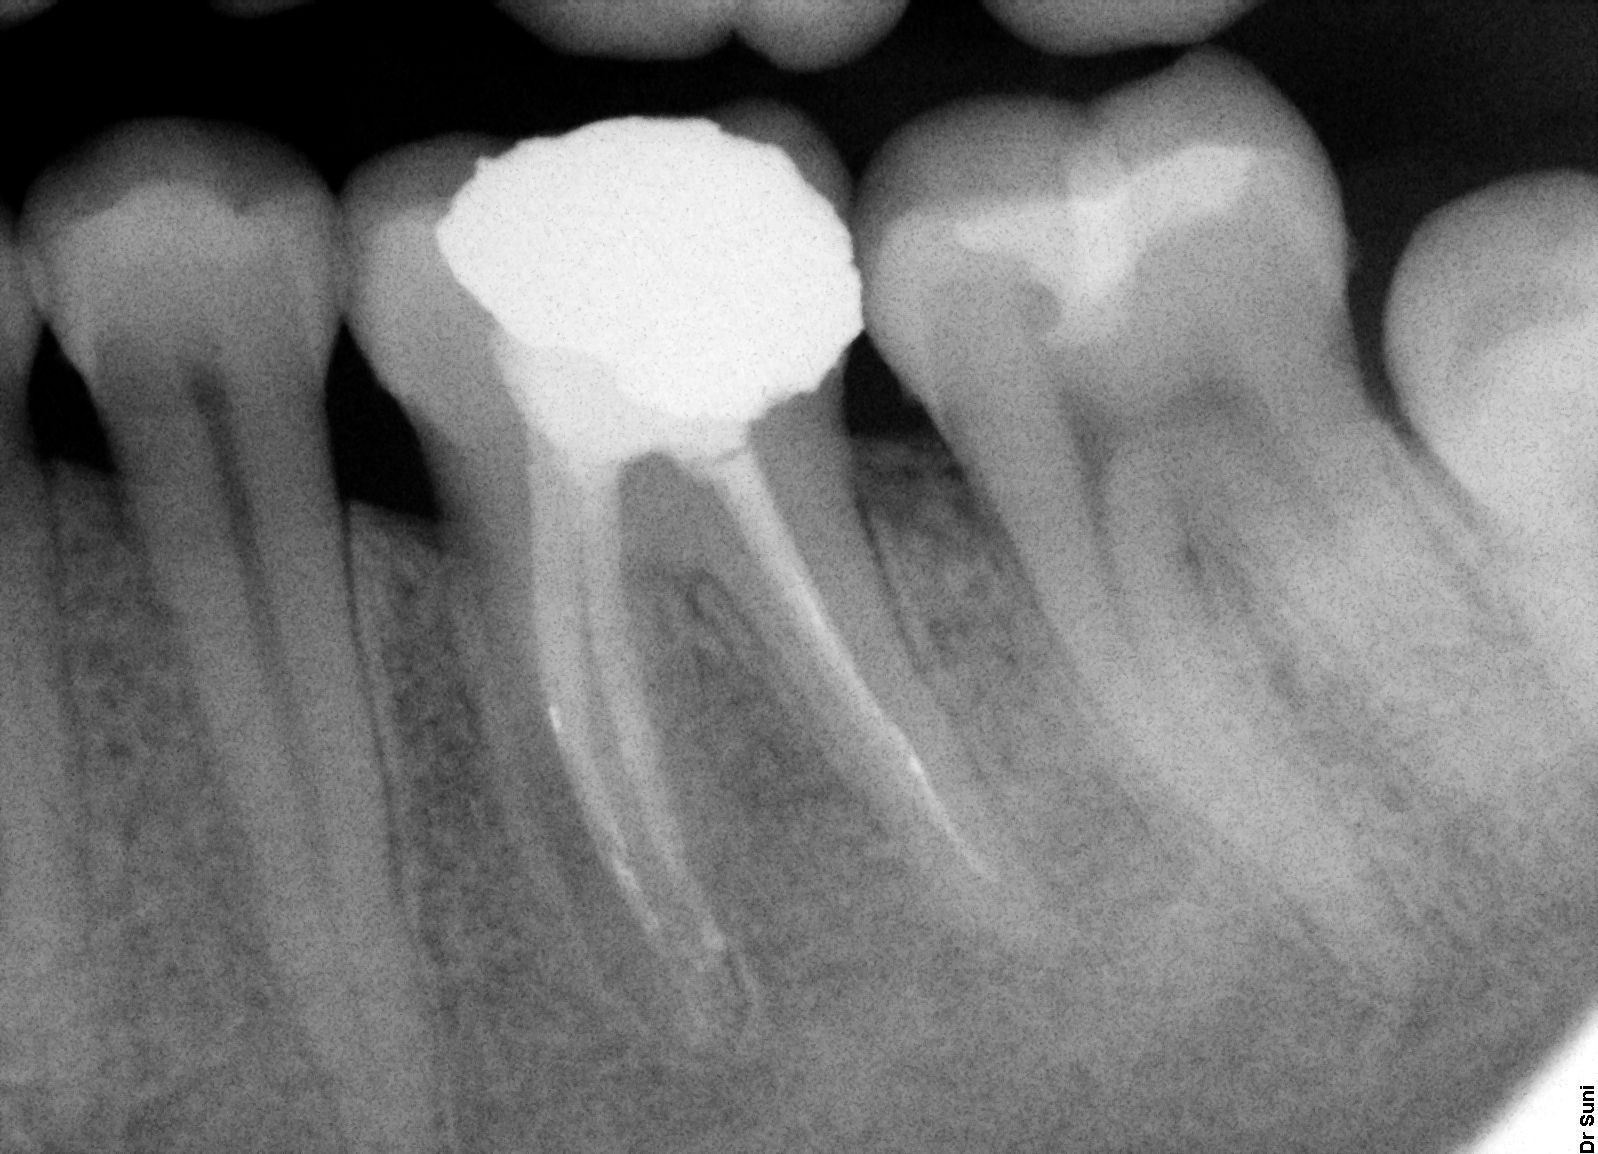

Reendodoncie u zubu s pulpoparondotální lézí

Zub 36 byl příčinou submukózního abscesu s iniciální viklavostí 2-3st,v roce 2009 po ošetření kořenových kanálků a nezcela RTG uspokojivém zaplnění, došlo během dvou let k úplnému vyhojení léze (rok 2011). Klinicky zub klidný bez známek zánětu a patologikcé viklavosti.